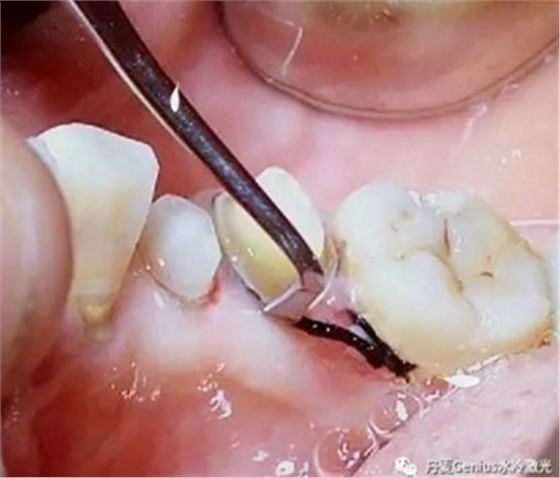

牙周病,潔治

在進(jìn)行潔治前,將表麻凝膠涂于牙齦上,待3分鐘后操作。也可根據(jù)需要,補(bǔ)充局麻。